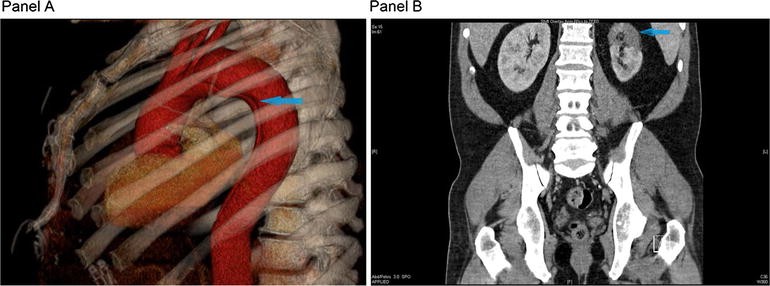

Follow-up CT scan. CT scan obtained three and a half months after discharge demonstrated a Stanford type B aortic dissection with the intimal flap originating just distal to the origin of the left subclavian artery and extending to the descending portion of the thoracic aorta (Panel A, 3D reconstruction, blue arrow). There was no involvement of the great vessels. A marked perfusion defect in the upper pole of the left kidney with associated interval atrophy of the left upper pole was seen (Panel B, blue arrow). Unchanged aneurysmal dilatation of the proximal abdominal aorta, measuring 3.3 × 3.3 cm, was present